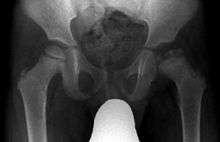

| X ray of Legg–Calvé–Perthes disease of the right hip (left side of X-ray) | |

X-rays of the hip may suggest and/or verify the diagnosis. X-rays usually demonstrate a flattened, and later fragmented, femoral head. A bone scan or MRI may be useful in making the diagnosis in those cases where X-rays are inconclusive. Usually, plain radiographic changes are delayed 6 weeks or more from clinical onset, so bone scintigraphy and MRI are done for early diagnosis. MRI results are more accurate, i.e. 97 to 99% against 88 to 93% in plain radiography. If MRI or bone scans are necessary, a positive diagnosis relies upon patchy areas of vascularity to the capital femoral epiphysis (the developing femoral head).